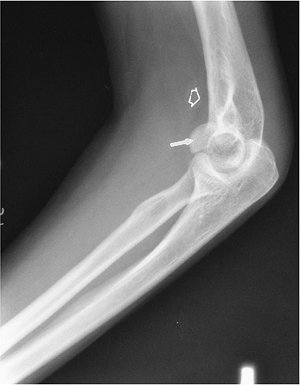

![]() |

FIGURE 8-8 Lateral view of the elbow demonstrating a capitellar fracture (arrow) and displaced fat pad (open arrow).